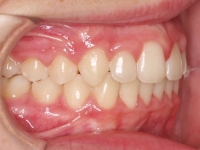

El paciente A.J. de 11 años, acude a nuestra consulta con apiñamiento maxilar importante. El canino lateral (12) está en mordida cruzada. Presenta una Clase II molar y canina, y la línea media está desviada. Se realizó un tratamiento con brackets autoligables metálicos de smartclip 022. La duración del tratamiento fue de 22 meses.

El paciente actualmente ha terminado el tratamiento con brackets y lleva una contención fija de 2-2 en maxilar y 3-3 en mandibular; para complementar también lleva una férula ESSIX durante la noche.

INICIO FINAL